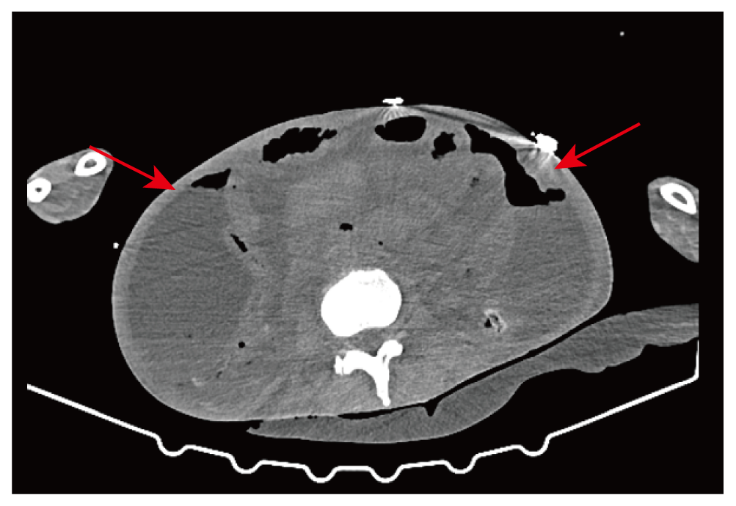

病史摘要:59 岁男性,十余年前行左踝关节囊肿切除术,约 20 年前行结扎术。因左侧睾丸肿块一年多入院。三年前因上腹疼痛不适就诊,胃镜发现胃角溃疡,活检提示低分化腺癌(印戒细胞癌),后行腹腔镜下远端胃切除术等,术后病理确诊为中低分化远端胃腺癌。 诊疗过程:术后接受 SOX 方案辅助化疗,因不良反应后续单药替吉奥胶囊治疗,还接受过放疗。此次入院查体左侧睾丸肿大等。实验室检查 CA19-9、C